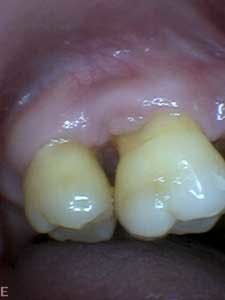

Dental examination revealed gingival swelling and bleeding on probing. Periodontal probing showed moderate-to-deep pocket depths in all posterior teeth (figures 1–3). Generalized bone loss was observed on radiographs (figures 4–6). Tooth vitality and percussion tests were negative. Teeth 2, 3, 31, 14, and 15 had Class III mobility. The patient was diagnosed with Type IV chronic adult periodontitis. Treatment options were discussed, and, after explanation, the patient agreed to the LANAP procedure.

Patient presentation before LANAP treatment (figures 1–6)